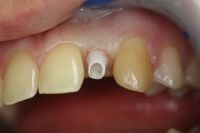

In molti casi, grazie alla tecnologia ad ultrasuoni, è possibile evitare l'uso del trapano per inserire gli impianti, rendendo la procedura più piacevole e sicura per il paziente. La tecnologia "piezosurgery" protegge da lesioni accidentali i nervi, i vasi sanguigni e qualunque struttura sensibile nella zona. Dire "implantologia a carico immediato" significa indicare quella tecnica che permette di inserire gli impianti dentali in titanio e di caricarli, ovvero di fissarvi sopra i denti, nella stessa seduta o comunque entro 24-48 ore dal primo intervento.

Non sempre ogni dente necessita di un proprio impianto, ad esempio nella figura accanto possiamo vedere quattro denti sostenuti da tre soli impianti.